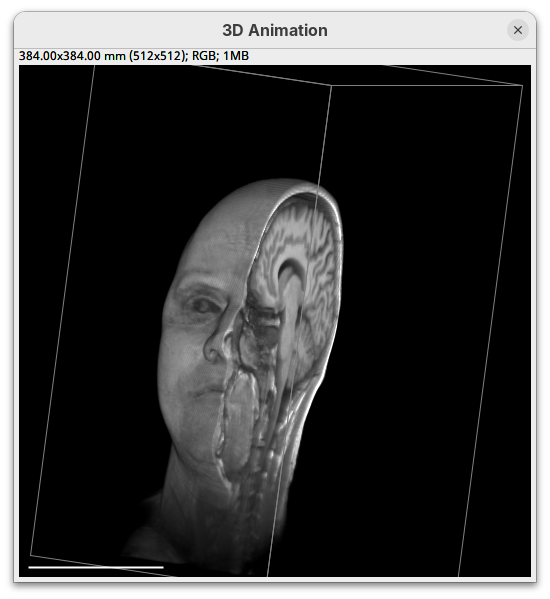

3Dscript

3Dscript is a GPU-accelerated Fiji plugin to generate animations of 3D/4D data (Schmid et al. 2019). It supports stacks with multiple channels and timepoints, has several options to control the rendering appearance, allows custom transformations and cropping of the data, and generates animations using a natural language, which is great to have precise control over the animation. 3Dscript is also incredibly fast to generate the animations and doesn’t require a lot of memory since the datasets can be opened as virtual stacks (more about this below).

This tutorial covers the basics for generating animations for 3D and 4D datasets. For more detailed information and documentation please refer to 3Dscript’s wiki.

To get started, make sure the head dataset is still open.

- Go to

Plugins>3Dscript>Interactive Animation.

Two new windows will open: 3D Animation with the initial rendering of the data and Interactive Raycaster with all the fields to control the rendering parameters.

Transformation

The transformation menu has controls for rotating, translating, and scaling the sample. We can either add values or manually interact with the 3D Animation window to reorient the sample. Let’s try the latter.

- Left-click on the head and move it around.

That’s a great way to see your sample from different angles. And note that the values in the Transformation panel get updated every time you move the sample interactively. In this way you can roughly position the sample and then check and update the precise values for the target transformation.

- Press

Resetand change theRotation Yto180to look at the right side of the head.

- Now change

Scaleto5andTranslation Xto-500to focus on the nose.

- Press

Resetto return the sample to its original position.

Cropping

Another useful 3Dscript option is the ability to crop the bounding box to show the inside of the sample. We can do it in the XYZ directions or in the near/far axis, defined from the user point of view.

- Set the Z range minimum value to

60(you can also drag the slider) to slice the sample through the Z axis.

- Now rotate the sample to see the cropped region from other angles.

- Set the Y range

minto125and rotate around.

- Finally, reset the position and cropping parameters and set the Near/Far minimum to

0and move the sample around to see the dynamic reslice of the sample with this cropping parameter.

- Reset transformations and cropping parameters.